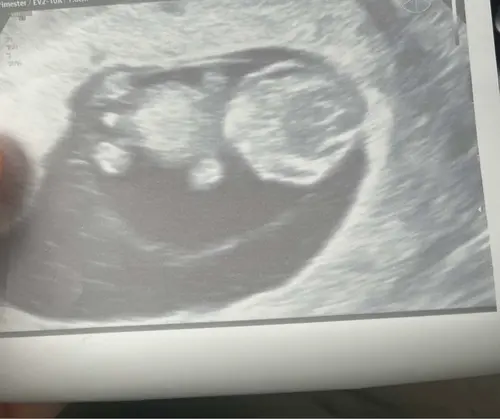

8w 🤩